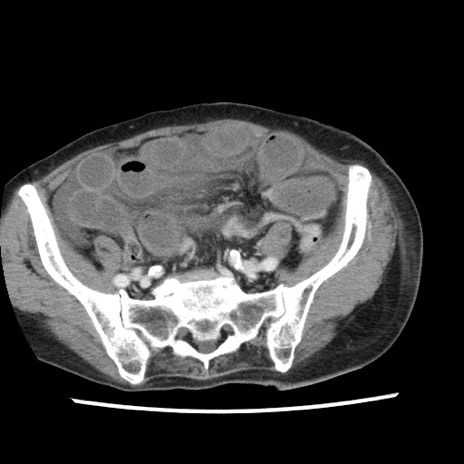

症例1(横断像)

【症例】80歳代女性

【主訴】腹痛

【現病歴】8時間前から腹痛あり来院。

【既往歴】糖尿病、脂質異常症、子宮体癌にて子宮全摘術

【身体所見】意識清明・会話良好だが腹痛で苦悶様、全腹部にわたって反跳痛と圧痛あり

【データ】WBC 13600、CRP 0.14、LDH 224、CK 90